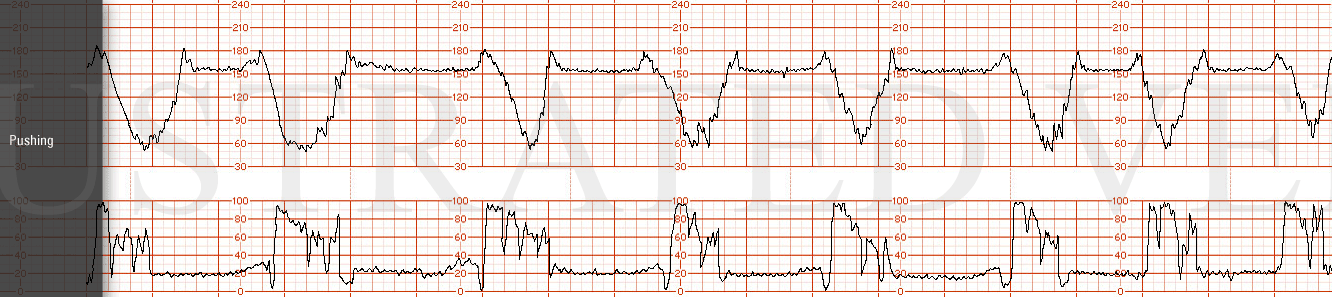

STRIP 70

1. 1st panel:

Tracing to show 140 bpm with average variability and no decelerations. Five 50-second contractions noted in 20 minutes of observation. (1st and 2nd contraction 10sec less, 5th 30secs less

2nd panel:

Panel: 20-minute of FHR strip.

Contractions:11 in 20 minutes, each lasting +/- 50-55 seconds. (1st 3rd, 4th, 6th, 7th, 8th, 10th and 11th too long 10-15 secs off)

Baseline +/- 165 bpm with minimal variability

Four mild to moderate, (but not unusual variable decelerations down to range of 105 to 125 bpm at minute 4, 11, 17 minutes, each with duration varying between 25-35 seconds.- with prompt return to baseline. There is no progression in depth or duration of decelerations – random. (1st 2nd more abrupt, 1st deeper, 4th more abrupt and deeper)

There are no spontaneous accelerations.

Indicate scalp stimulation at minute 18 with no resultant acceleration